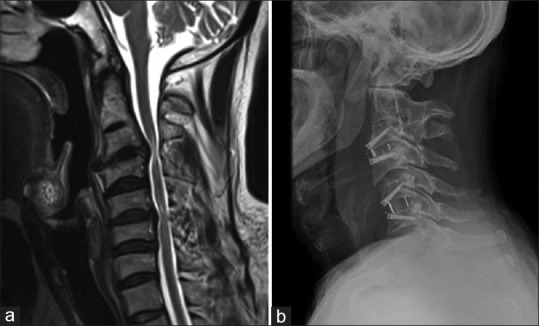

Methods: Fifty-two patients who underwent management of NCDDD and two-level contigious disc disease (CDD) over 6 years from 2014 to 2020 were included in the study. There were 44 male and 8 female patients with a mean age of 46.75 years. These patients were divided into two groups: Those who underwent contiguous discectomy and those who underwent skip discectomy with either anterior cervical discectomy (ACD) alone, ACD and fusion (ACDF), or ACDF with plating based on individual pathology and surgeon preference. Outcomes were assessed using clinical parameters such as modified Japanese Orthopaedic Association Score (mJOAS) and Nurick grade and radiological parameters such as disc height improvement, spinal alignment change, and fusion rates.

Results: The overall mean duration of follow-up was 15.23 ± 23.69 months, with a clinical follow-up period of 23.87 ± 21.51 months and a radiological follow-up period of 7.57 ± 5.91 months, with follow-up in Group 1 being 24.67 ± 23.17 months and in Group 2 being 20.03 ± 10.53 months. The mean blood loss in Group 1 was 200.47 mL; in Group 2, it was 172 mL. The preoperative mJOAS was 10.19 ± 3.16, and the postoperative mJOAS was 12.73 ± 2.92 (P = 0.001). Nurick grade showed improvement from a preoperative mean score of 4.23 ± 1.02-3.65 ± 0.88 postoperatively (P < 0.001). Statistically significant improvement in intervertebral height at superior and inferior levels was observed. Outcomes for Skip discectomy regarding mJOAS, Nurick grade, radiological parameters, fusion, and complication rates were noninferior to contiguous discectomy and fusion.

Conclusion: Skip discectomy has a similar benefit and risk profile and is noninferior compared to contiguous discectomy in addition to the preservation of intermediate disc integrity.